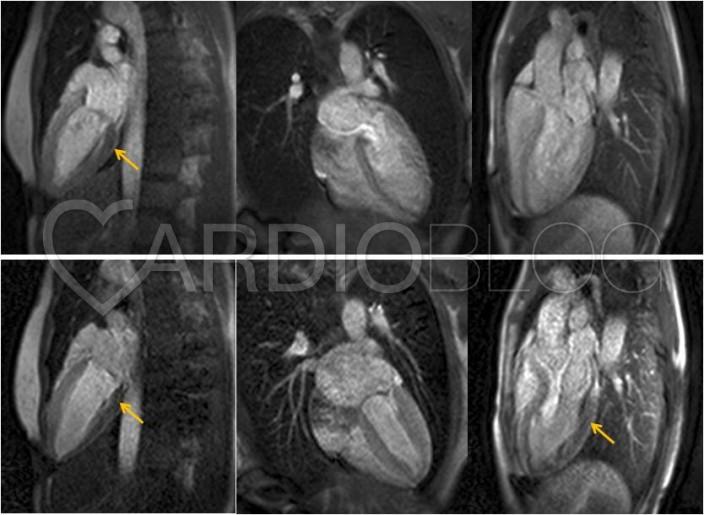

A perfúziós zavar mértékének, valamint a shunt áramlás megítélésre stressz perfúziós szív MRI vizsgálatot végeztünk, mely septalisan és az anterior falon subendocardialis, inferior, inferolateralis régióban transmuralis jelleggel indukálható markáns perfúzió zavart írt le. Az anomáliás CX-en retrográd vezetett shunttérfogat a szisztémás keringés 10%-a. Fontos körülmény, hogy a shuntolt vérmennyiség abszolút értékben a terhelés hatására nem változik.